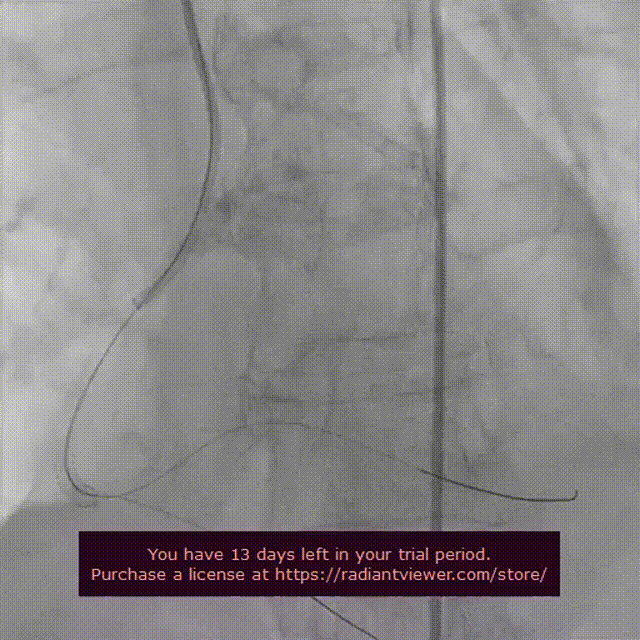

释放后造影观察反流消失,测压显示压差由术前的56mmhg下降至仅8mmhg。

瓣膜释放完毕后造影